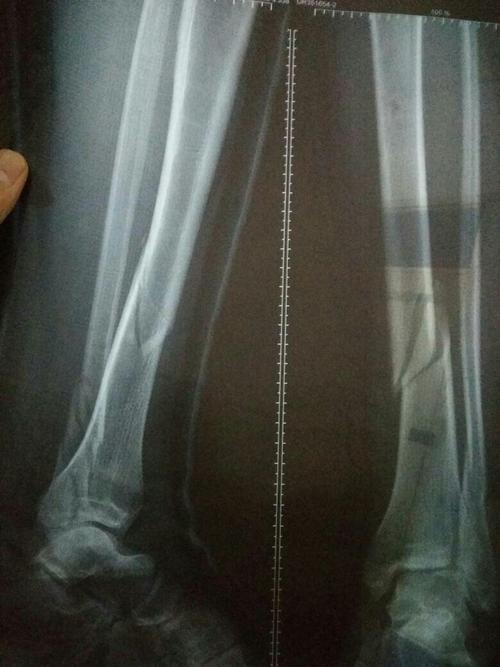

骨痂片子,长了骨痂的x光片图

是外踝骨折有碎片,但是不知道自己是哪里看不懂,想看下骨折线骨痂在哪

45天拍的片子,肉骨长了骨痂,胫骨没长,还用石膏固定吗?

术后三个月,x光片可见骨痂形成,患者恢复良好!家属满意!继续观察!

09-2-20治疗后55天.骨痂形成良好,局部无压痛和纵扣痛,去骨牵引.

胫腓骨骨折